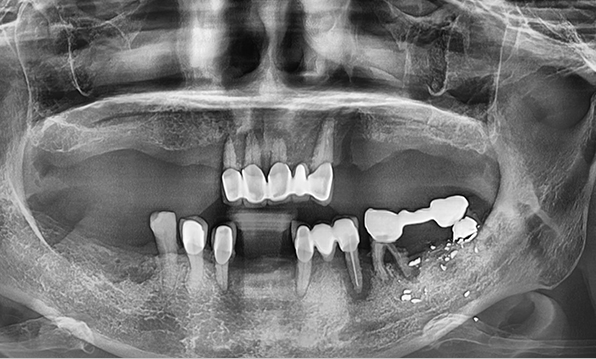

잇몸뼈가 얇은 상태

-

잇몸뼈 충분히 이식 후 임플란트 식립

성공을 위한 노하우, 잇몸뼈 재건 기술

전체 임플란트를 해야하는 환자들은

대부분 고령의 환자들로 오랜 틀니 사용

또는 노화로 인해 치조골이

거의 남아있지 않는 경우가 많습니다.

이 때, 치조골 이식을 병행하여 잇몸뼈 재건 후 안정적인 임플란트 식립을 하고 있습니다.